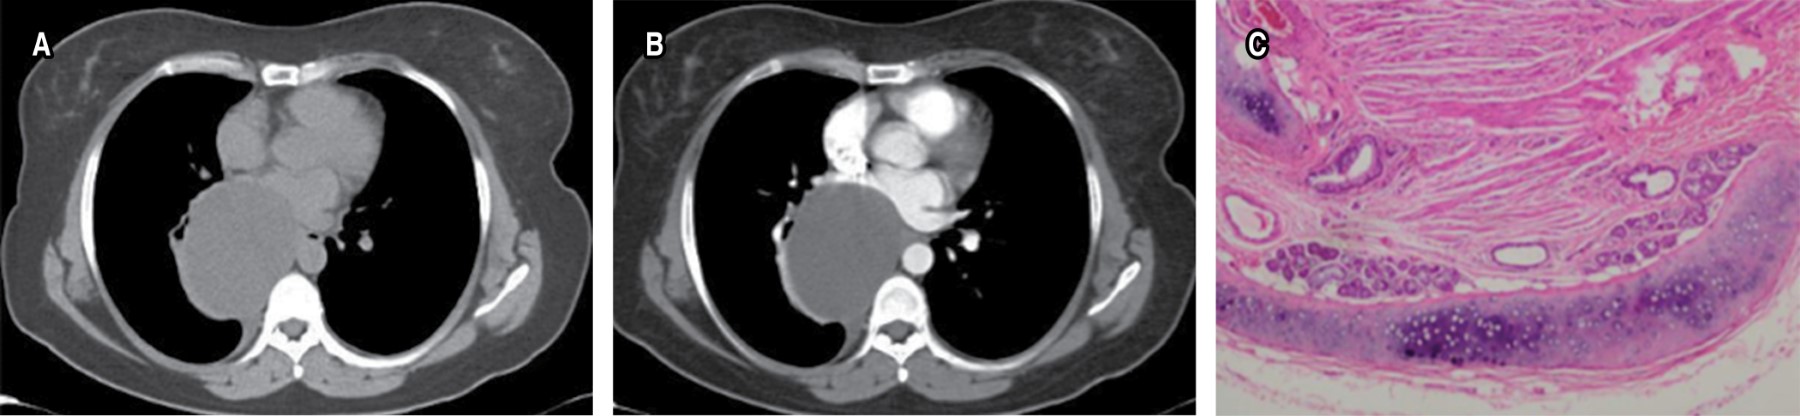

Entre los diagnósticos diferenciales se encuentran las masas mediastinales de contenido graso, así como las lesiones focales de contenido graso como la necrosis grasa mediastinal, caracterizada por mostrar un nido de atenuación grasa yuxtapericárdica rodeada de tejido inflamatorio, es el análogo de la apendagitis epiploica en abdomen, se acompaña de derrame pericárdico y atelectasias adyacentes. La necrosis grasa mediastinal ocurre con frecuencia en hombres de 40 a 50 años de edad, es autolimitada, los síntomas son similares a los percibidos en tromboembolia pulmonar e infarto agudo al miocardio, desaparecen en 48 a 72 horas.13 Se trata de grasa histológicamente normal, muy fácil identificarla en estudios de resonancia magnética, se observa aumento de intensidad de señal en secuencias de T1 y T2, con similitud a la grasa subcutánea cuando es comparada.

Son lesiones quísticas adquiridas, representan 0.1% de todos los quistes mediastinales. Están compuestos de una cápsula fibrosa: periquiste. El quiste verdadero tiene una pared delgada compuesta por dos capas adherentes, el endoquiste laminado y endoquiste de tapizamiento delicado, de los cuales cuelgan los quistes hijos. Tienen predilección por el mediastino anterior y se muestran como lesiones quísticas con quistes hijos (Figura 11).

En la IRM los hallazgos son muy característicos, el periquiste es hipointenso en T1 por su componente fibroso. El quiste madre o verdadero es de intensidad de señal intermedia en T1 y el quiste hijo tendrá menor intensidad de señal en T1 que la matriz del quiste madre. En imágenes potenciadas en T2, el periquiste permanecerá hipointenso, y en T2 los quistes madre e hijos presentarán la misma intensidad de señal alta.